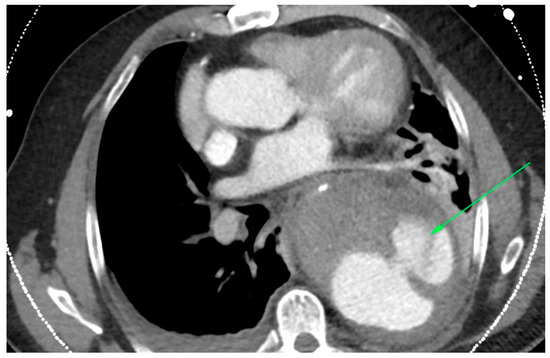

In the primary aortic group, 64% had an aneurysm (Figure 1), 18% had an aortic dissection, and 18% a PAU. In the secondary aortic group, 17% had an iatrogenic aortic lesion after spine surgery, 58% a trauma, and 25% an aortoesophageal fistula (Figure 2 and Figure 3). All patients underwent CT scan for diagnosis and after the surgery (Figure 4). Percutaneous access was performed in 31.8% of the patients in the primary aortic and 41.7% in the secondary aortic group (p = 0.566). An operation in local anesthesia was performed in 31.8% of the patients in the primary aortic group and 25% in the secondary aortic group (p = 0.677). Median duration of hospital stay was longer in the primary aortic group compared to the secondary aortic group (14.5 vs. 8 days, p = 0.746). Simultaneous surgery was similarly frequent in both groups (22.7% vs. 25%, p = 0.881). Procedures included: hepatic artery bypass, aortic arch debranching, surgical treatment of a pelvic fracture, thoracotomy, bowel resection, trepanation, ECMO implantation, and splenectomy.

Figure 2.

CT-scan of a thoracic aortic aneurysm rupture with an aortoesophageal fistula (green arrow).

In the patients included in our analysis, there were three patients treated for an aortoesophageal fistula. Only one patient, treated for primary fistula with esophagectomy and TEVAR in the same procedure, survived (Figure 2, Figure 3, Figure 4 and Figure 5). This patient is still alive and in follow-up. The other two patients treated for a secondary fistula due to anastomotic leak after esophagectomy for esophageal cancer died after TEVAR. The incidence of an aortoesophageal fistula after TEVAR for primary aortic pathologies is low, as demonstrated in the European Registry of Endovascular Aortic Repair Complications (1.5%). In this cohort, the highest 1-year survival (46%) could be achieved via an aggressive treatment, including radical esophagectomy and aortic graft replacement [41]. In our patient population, we did not treat patients with a secondary fistula after TEVAR. In a 2014 review, 55 articles were included which reported on 72 patients treated with TEVAR for aortoesophageal fistula. Similar to our data (100% technical success rate), the technical success rate was 87.3%. Nevertheless, the overall 30-day mortality was significantly lower (19.4%) than in our series [42]. In a 2009 meta-analysis, 43 patients with aortoesophageal fistula were identified. Mortality after TEVAR was 19%. Patients who underwent esophageal surgery in the first month after TEVAR had lower fistula-related mortality during 6 months of follow-up compared to the other patients (p = 0.018) [43].